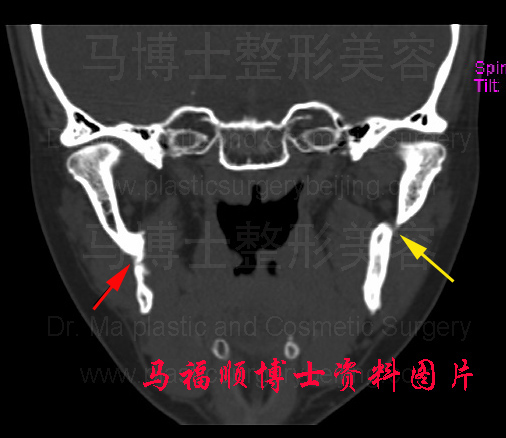

下面图片是马福顺博士在临床工作中见到的一例下颌骨不完全性骨折、断端对位不正、对线不齐的CT片。受术者一年前进行过下颌骨整形美容手术,无明显自觉症状,找马福顺博士进行颧骨颧弓整形手术时CT检查发现有下颌骨不完全性骨折。由于其骨折线没有跨过下颌骨的应力线,而且对下颌骨的功能和面部外形没有造成不良影响,所以马福顺博士只是告知其有不完全性骨折,但对手术效果和功能没有造成影响,不建议进行任何手术复位和固定。

正常下颌骨与下颌骨骨折的冠状切面CT图片。左侧者为正常下颌骨切面,可见左右两侧的下颌骨升枝切面骨骼完整。右侧图片下颌骨的升枝不再连续箭头所指为下颌骨的骨折线,红色箭头所指的右侧下颌骨骨折断端间隙较小,黄色箭头所示的左侧下颌骨折断端之间有明显的间隙,对位对线均不好。这种情况下两断端不能愈合。